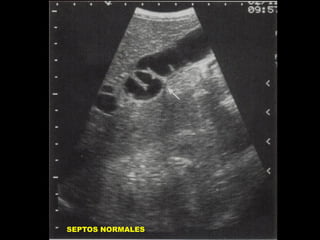

SEPTOS DENTRO DE LA

VESICULA BILIAR

• PLIEGUES VESICULARES

NORMALES.

SEPTOS NORMALES